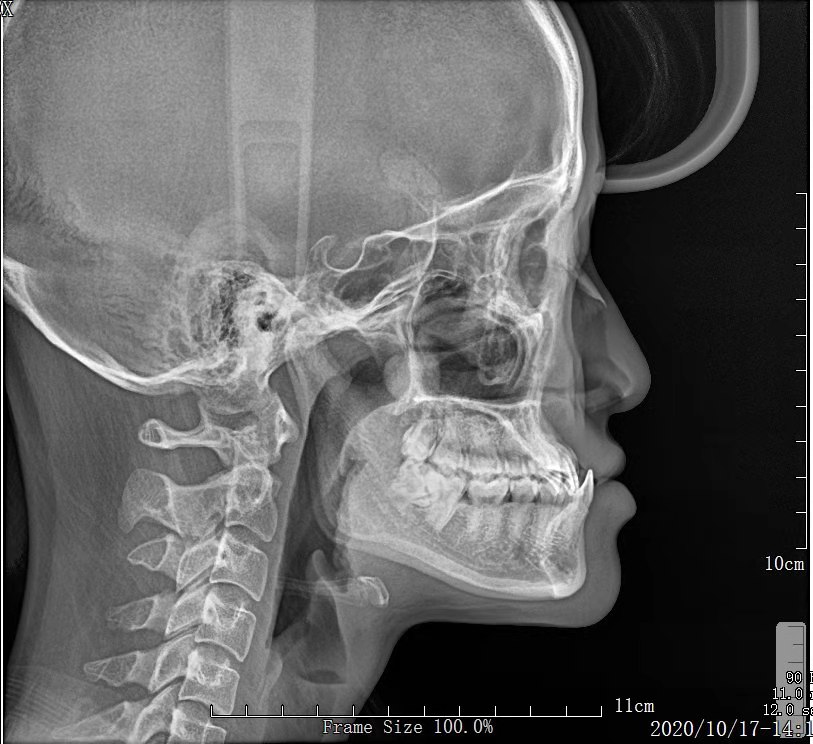

- 首先要找靠谱的医生去面诊,详细了解一下自己 的情况,面诊检查【拍片、照相、取牙模】 后面有详细介绍

PS: 前期准备工作包括(全景片 ,头颅侧位片 ,CT ,6张口内 照片,6张面相照 , 模型,补牙,洁牙…)